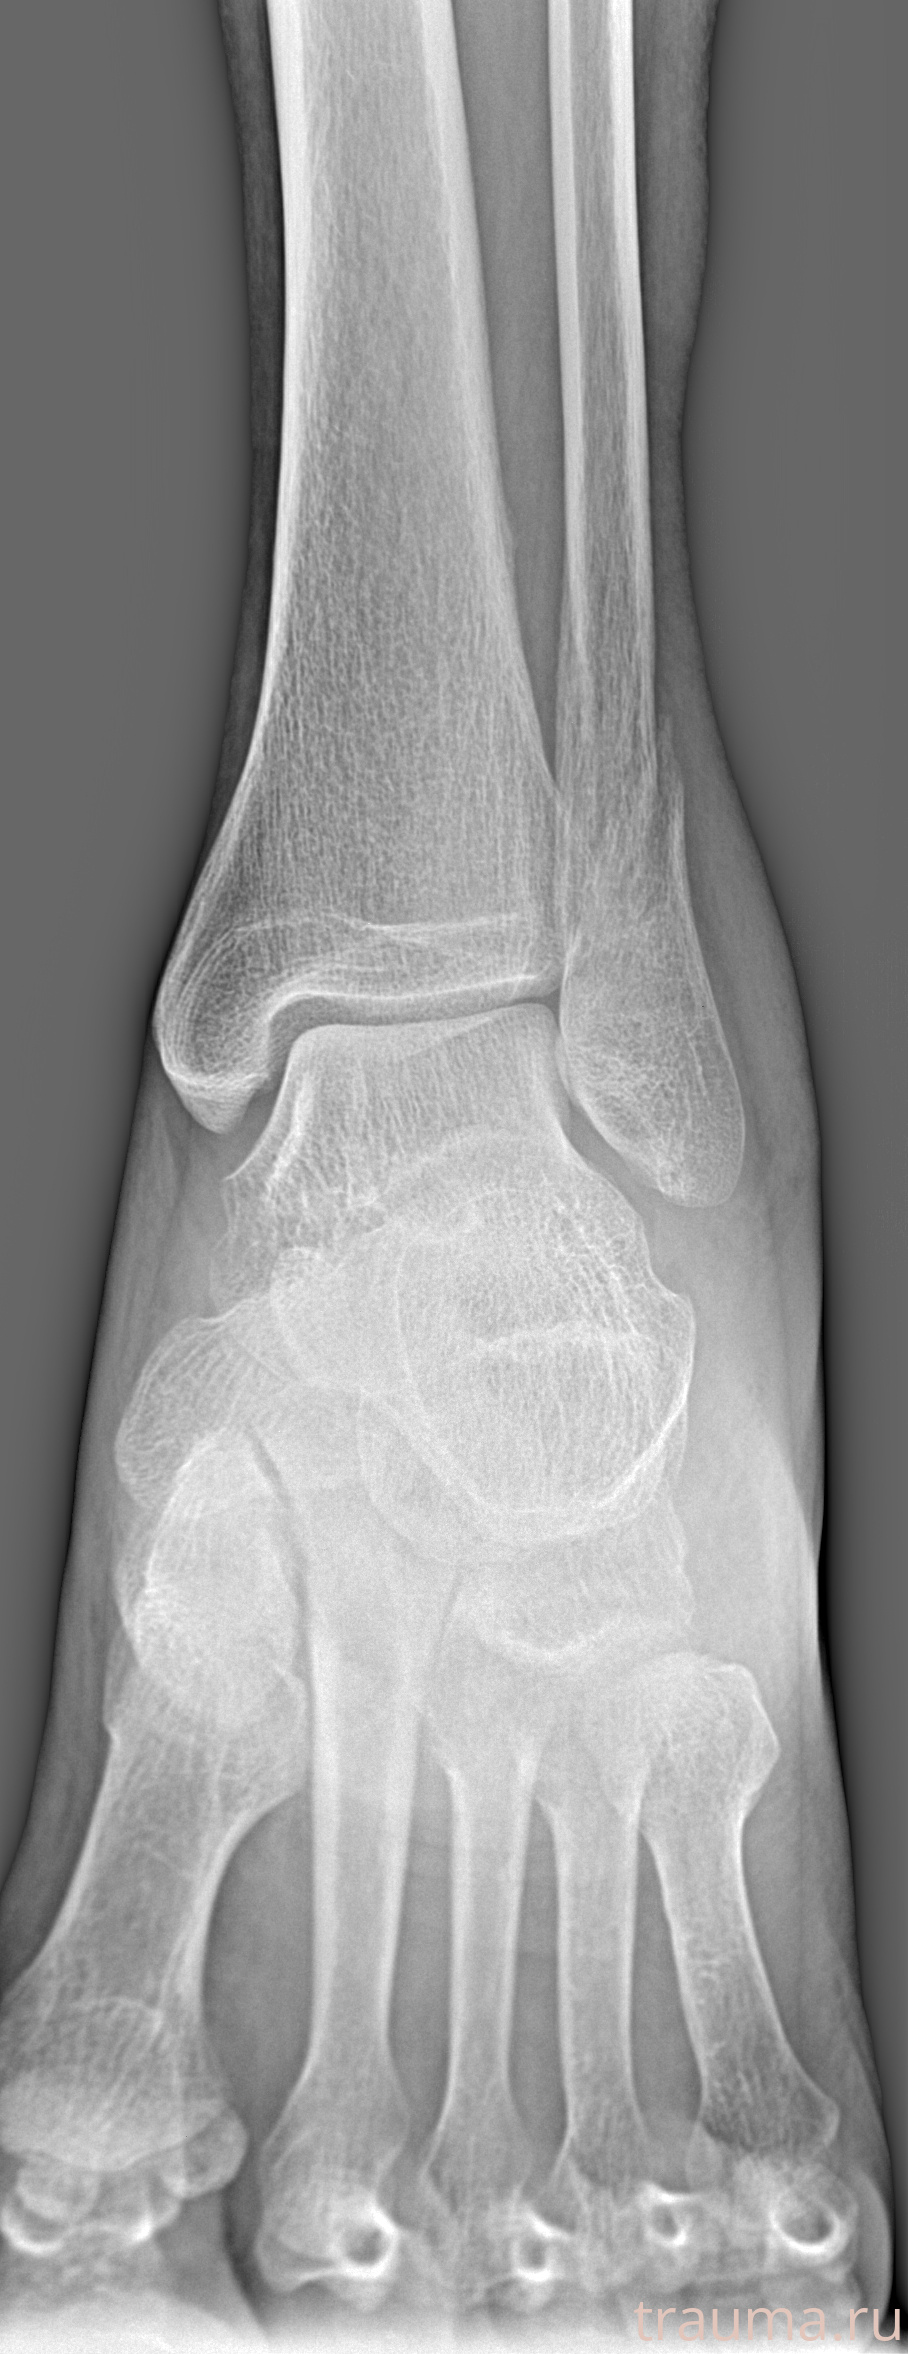

Рентгенограммы

Рентген на дому: по вашему адресу приезжает врач-рентгенолог, травматолог-ортопед с мобильным рентгеновским аппаратом, проводит диагностику травмы или заболевания, делает необходимые рентгенограммы, дает рекомендации по дальнейшему лечению. Получить качественные снимки в домашних условиях возможно благодаря уникальной методике, разработанной МосРентген Центром для института  Склифосовского

Яркость: 1   Контраст: 1   Инвертировать: 0 Увеличение: 1

Перетаскивайте мышь вверх/вниз для контраста, влево/право для яркости. Прокрутка колесом изменяет масштаб. Нажмите Сбросить для возврата к исходному изображению. При увеличении держите мышь в той области, которую хотите рассмотреть.